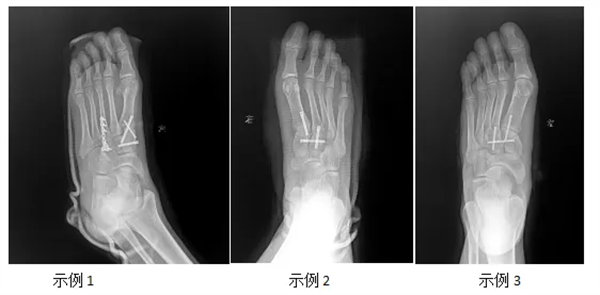

近期我院骨三科接診并治療多例足部外傷后導致的Lisfranc損傷。在科室醫生細致診查和規范的手術治療后均順利康復出院。

手術治療:若存在骨折移位、韌帶撕裂嚴重或關節不穩定,需手術復位骨折、固定關節,必要時修復或重建韌帶,以恢復足部穩定性。